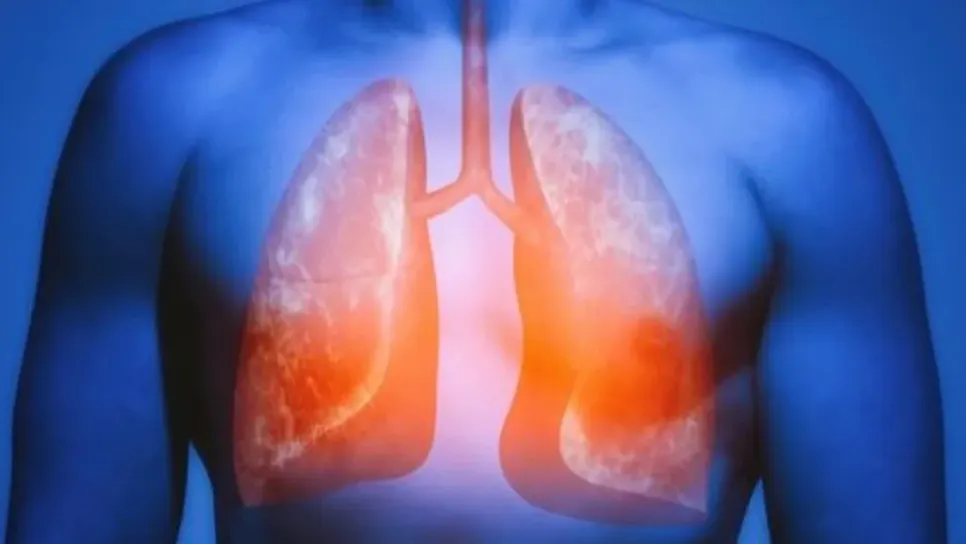

Getty Images الخلايا القليلة التي تنجو من طفرات الخلايات السرطانية يمكنها إعادة إصلاح الرئتين اكتشف العلماء قدرات "سحرية" تقريبا لرئة الإنسان تمكنها من إصلاح نفسها والتصدي للطفرات السرطانية الناجمة عن التدخين. وبحسب المعلومات السابقة فإن الطفرات التي تؤدي إلى سرطان الرئة كانت تعتبر دائمة وتستمر حتى بعد الإقلاع عن التدخين.لكن النتائج المفاجئة، التي نُشرت في مجلة "نيتشر"، تكشف أن الخلايا القليلة التي تنجو من طفرات الخلايات السرطانية يمكنها إعادة إصلاح الرئتين.وقد لوحظ هذا التأثير حتى في المرضى الذين يدخنون علبة سجائر كاملة يوميا على مدار 40 سنة كاملة ق...